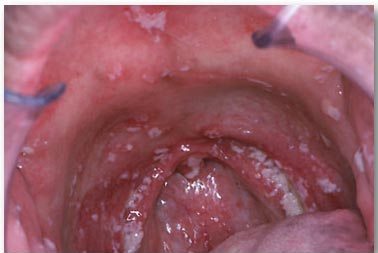

Giáo sư Henriques và nhóm của cô - người đã công bố nghiên cứu này trong trang Xã hội của Tạp chí Ứng Dụng Vi Trùng Học Ngày Nay - xem xét việc sử dụng các kích cỡ khác nhau của các hạt nano bạc để xác định khả năng diệt vi nấm Candida albicans và Candida glabrata. Hai vi nấm này gây ra các bệnh nhiễm trùng như bệnh tưa lưỡi và viêm vùng miệng ảnh hưởng đến khoảng bảy trong số mười người mang răng giả. Loại nhiễm trùng này điều trị đặc biệt khó khăn vì các vi nấm này liên quan đến sự hình thành màng sinh học.

Các loại nấm Candida gây bệnh tưa lưỡi - viêm